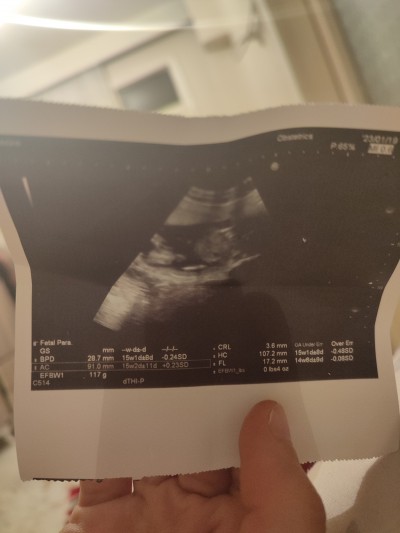

Kızlar bakıyorum da internetten bu haftalrda gramı 70 80 arası ama burda 117 yazıyor bu dmeek yada haftama göre ultrason kagidima bakarak söyleyebilir misiniz 15+1

Gebelik haftası 15+1

Evet kilosu 117 gram boyu baş çevresi hepsi ölçümüş burda ama bu haftada kilonun anlamı yok biliyorum anne olarak merak ediliyor ama doğuma yakın kilo çok daha önemli bnm 3.gebeliğim her gün dua ediyorum bebeğim sağlıklı ve küçük olsun ben dikişsiz ve rahat doğum yapayım diye zaten bebek doğduktan sonra anne karnında gibi endişe etmiyorsunuz acaba yediğim bebeğe mi gitti bana mı diye siz üstünüzle besliceksiz kilo kontrolü bizim elimizde olucak artık öyle düşünün şuanda bir annenin tek derdi çok kolay doğum geçirmek olmalı hepimiz sağlıkla kucaklarımıza almamız dileğğmle.